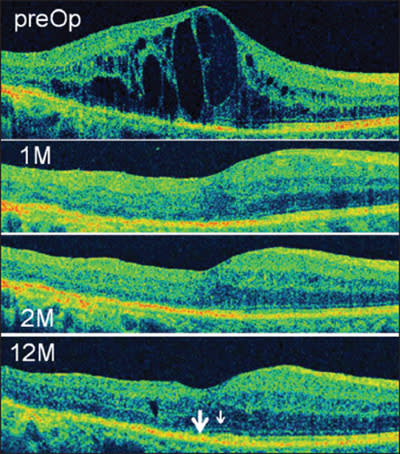

Figure 2. Central macular thickness decreased with restoration of normal foveal depression. As DME resolved, the IS/ OS (large arrow) and ELM lines partially regenerated (small arrow).

In subgroup analysis, the four eyes that did not experience improved CMT by month 12 did not experience improvement in vision. Representative longitudinal changes of cross-sectional SD-OCT images are shown in Figure 2. CMT generally decreased, with restoration of the normal foveal depression at 1 month, and as the DME further resolved, the IS/OS and ELM lines partially regenerated.

Among the 20 IS/OS(-) eyes, the average VA did not improve significantly by month 12. In a subgroup analysis, the seven eyes with decreased CMT at month 12 (baseline CMT: 527±175 μm, 12 months: 227±25 μm) did not experience improved VA (baseline VA: logMAR 0.89±0.22, VA at 12 months: logMAR 0.76±0.31). Despite restoration of foveal depression, the IS/OS did not reform, thereby suggesting a permanent loss of photoreceptor integrity (Figure 3).